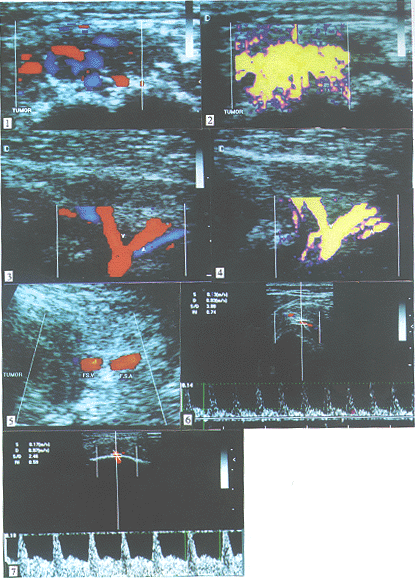

(1)肿瘤血管: 本组恶性肿瘤肿瘤内及/或肿瘤边缘均可探及动、 静脉血流, 且以动脉血流为主。 肿瘤血管多为浅层优势, 即肿瘤浅层或肿瘤边缘处血管多见而肿瘤深层或中心部血管相对减少或消失。 在骨皮质中断处常常见到小动脉穿行垂直进入髓腔内。 据血管PDI、CDFI表现可分为: ①团片状分布型-高血供型: 表现为肿瘤内血管密集分布, 迂曲扩张, 互相交通。 动态观察肿瘤内布满红、 蓝镶嵌的彩色血流信号, 或连接成团片状, 或见5个以上斑片状彩色像素或3条以上血管走行。 PDI显示更清晰, 形似火焰状(图1,图2)。 此型以骨肉瘤、 骨转移癌多见。 ②树枝状分布型-中血供型: 肿瘤内血管分布较上型稀疏, 走行似树枝, 可见1~2条血管走行或见3~5个斑点状彩色像素。 上述两型在恶性肌骨系统肿瘤占85%(51/60)。 PDI显示为清晰的树枝状血管, 恰似“圣诞树”样(图3,图4)。 此型多见于骨巨细胞瘤和部分骨肉瘤、 骨转移癌。 ③斑点状分布型-少血供型: 肿瘤内血管走行不清, 仅有1~3个斑点状彩色像素分布于强回声斑块表面或缝隙中。 PDI显示斑点状血流信号似天空闪烁之星。 此型可见于脊索瘤、 软骨母细胞瘤等恶性肿瘤, 共占15%(9/60)。

(2) 肿瘤与周围大血管及肿瘤表面血管: 在肿瘤附近有大血管时, 如股骨近、 远端、 肱骨近端等处恶性肿瘤, PDI、CDFI可清晰观察股动脉、 腋动脉等大血管与肿瘤界限是否清晰, 有无受侵。 恶性肌骨系统肿瘤常常显示肿物与血管壁界限不清、 受压移位、 包绕等征象(图5)。 PDI、CDFI表现为患侧大血管内彩色血流亮度增加或呈多彩状血流。 频谱形态与健侧不同, 常常为舒张末期流速较健侧加大。 肿瘤部位之皮下组织常常见到絮状或蚓状低回声带, 频谱显示为静脉怒张。 此表现以骨肉瘤多见。

1. PDI、CDFI同样可以鉴别肌骨系统良恶性肿瘤: 从血管分布来看, 恶性肌骨系统肿瘤血管血流色彩明亮丰富, 分布广泛, 可见迂曲扩张, 互相交通成片状或树枝状血流信号; 良性肌骨肿瘤以斑点状血流多见。 从频谱分析来看, 恶、 良性肌骨系统肿瘤收缩期血流峰值分别为27.34±11.78和15.40±8.44cm/s(P值<0.01); 阻力指数分别为0.77±0.08和0.61±0.10(P值<0.001)。 说明恶性肌骨系统肿瘤显示为高速高阻血流(图6), 良性肌骨系统肿瘤显示为低速低阻血流(图7)。

图1 CDFI显示肿瘤内血管密集分布,连接成团片状

图2 PDI显示更清晰,形似火焰状

图3 CDFI显示肿瘤内血管走行呈树枝状

图4 PDI显示为清晰的树枝状血管,恰似"圣诞树"样

图5 恶性肌骨系统肿瘤常常显示肿物与血管壁界限不清,受压移位,包绕等征象

图6 恶性肌骨系统肿瘤显示为高速高阻血流

图7 良性肌骨系统肿瘤显示为低速低阻血流